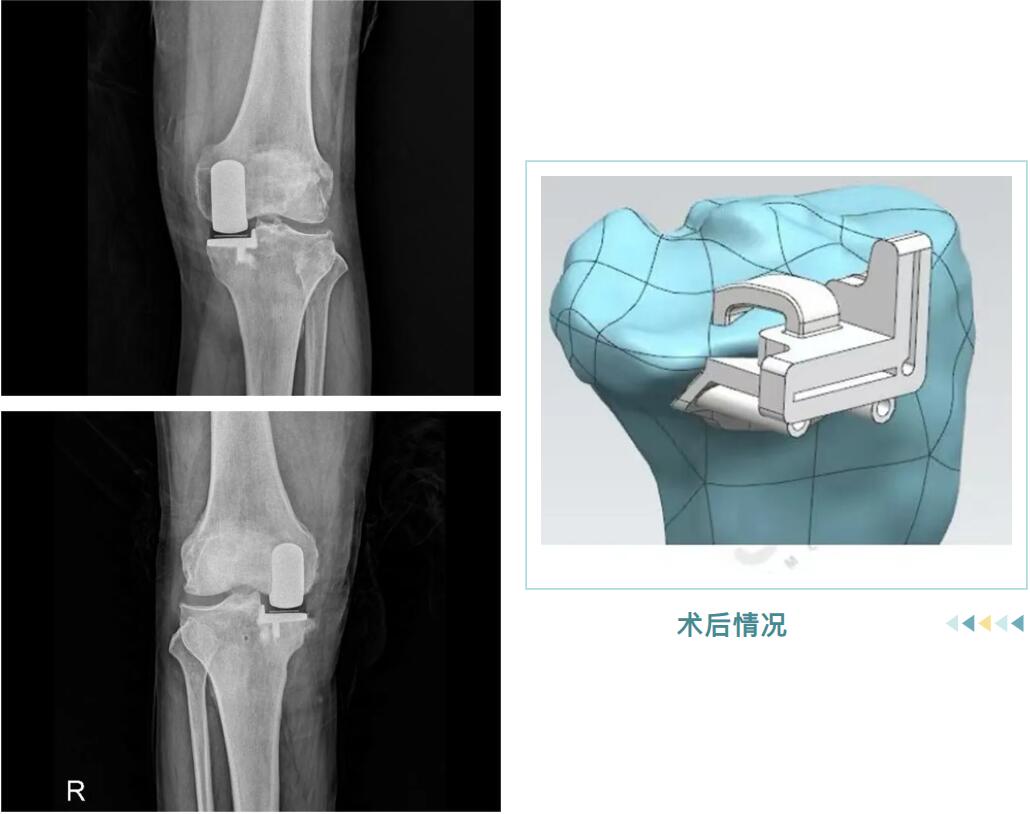

從精準的3D術前規(guī)劃,到羅院長團隊嫻熟的手術操作,再到術后個性化的康復指導,整個過程高效而順利。很快,邵阿伯的“羅圈腿”變直了,術后他輕松站起,行走時仿佛時光倒流十年。

術后情況